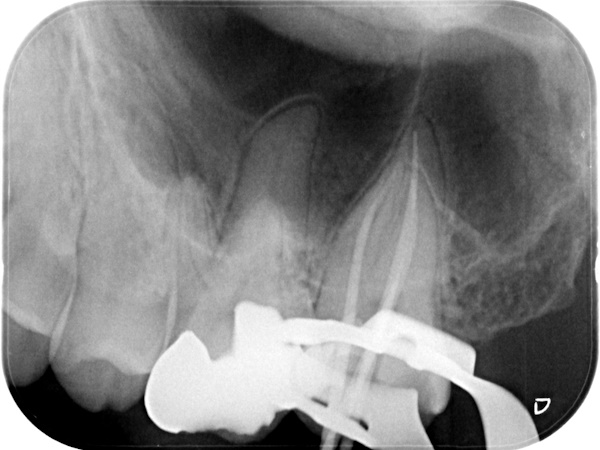

根管治療中(試適時)